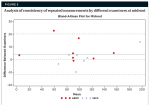

An analysis of internal consistency of repeated measurements by different examiners was accomplished by using the Bland-Altman plot, which is a visual representation of the differences between the two examiners. The intra-examiner measurements were more consistent than the interexaminer measurements. Crestal measurements by examiner 1 were typically higher than those of examiner 2 (Figure 4 through Figure 6).